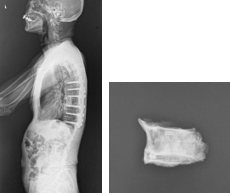

胸椎の腫瘍の場合

背中の皮膚を切開します。摘出する椎体の頭尾側にスクリューを設置し、ロッドで接続して脊椎を強固に固定します。後方より、肋骨を切除し、椎体前面、側面を剥離して、脊髄をよけながら、腫瘍に侵された椎体を一塊として摘出し、同部位に金属性のメッシュに局所骨あるいは腸骨を設置します。

腎癌の胸椎転移に対するTES手術